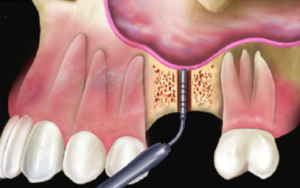

1. La quantità di osso tra il punto A ed il punto B non è sufficiente per inserire un impianto di dimensioni adeguate. |

2. Viene perciò preparato un foro d’accesso nel tessuto osseo. |

3. Fino ad arrivare all’inizio del seno mascellare. |

4. Quindi viene sollevata delicatamente la membrana, che ricopre internamente tutto il seno mascellare. |

5. Successivamente viene introdotto dell’osso artificiale all’interno del seno mascellare. |